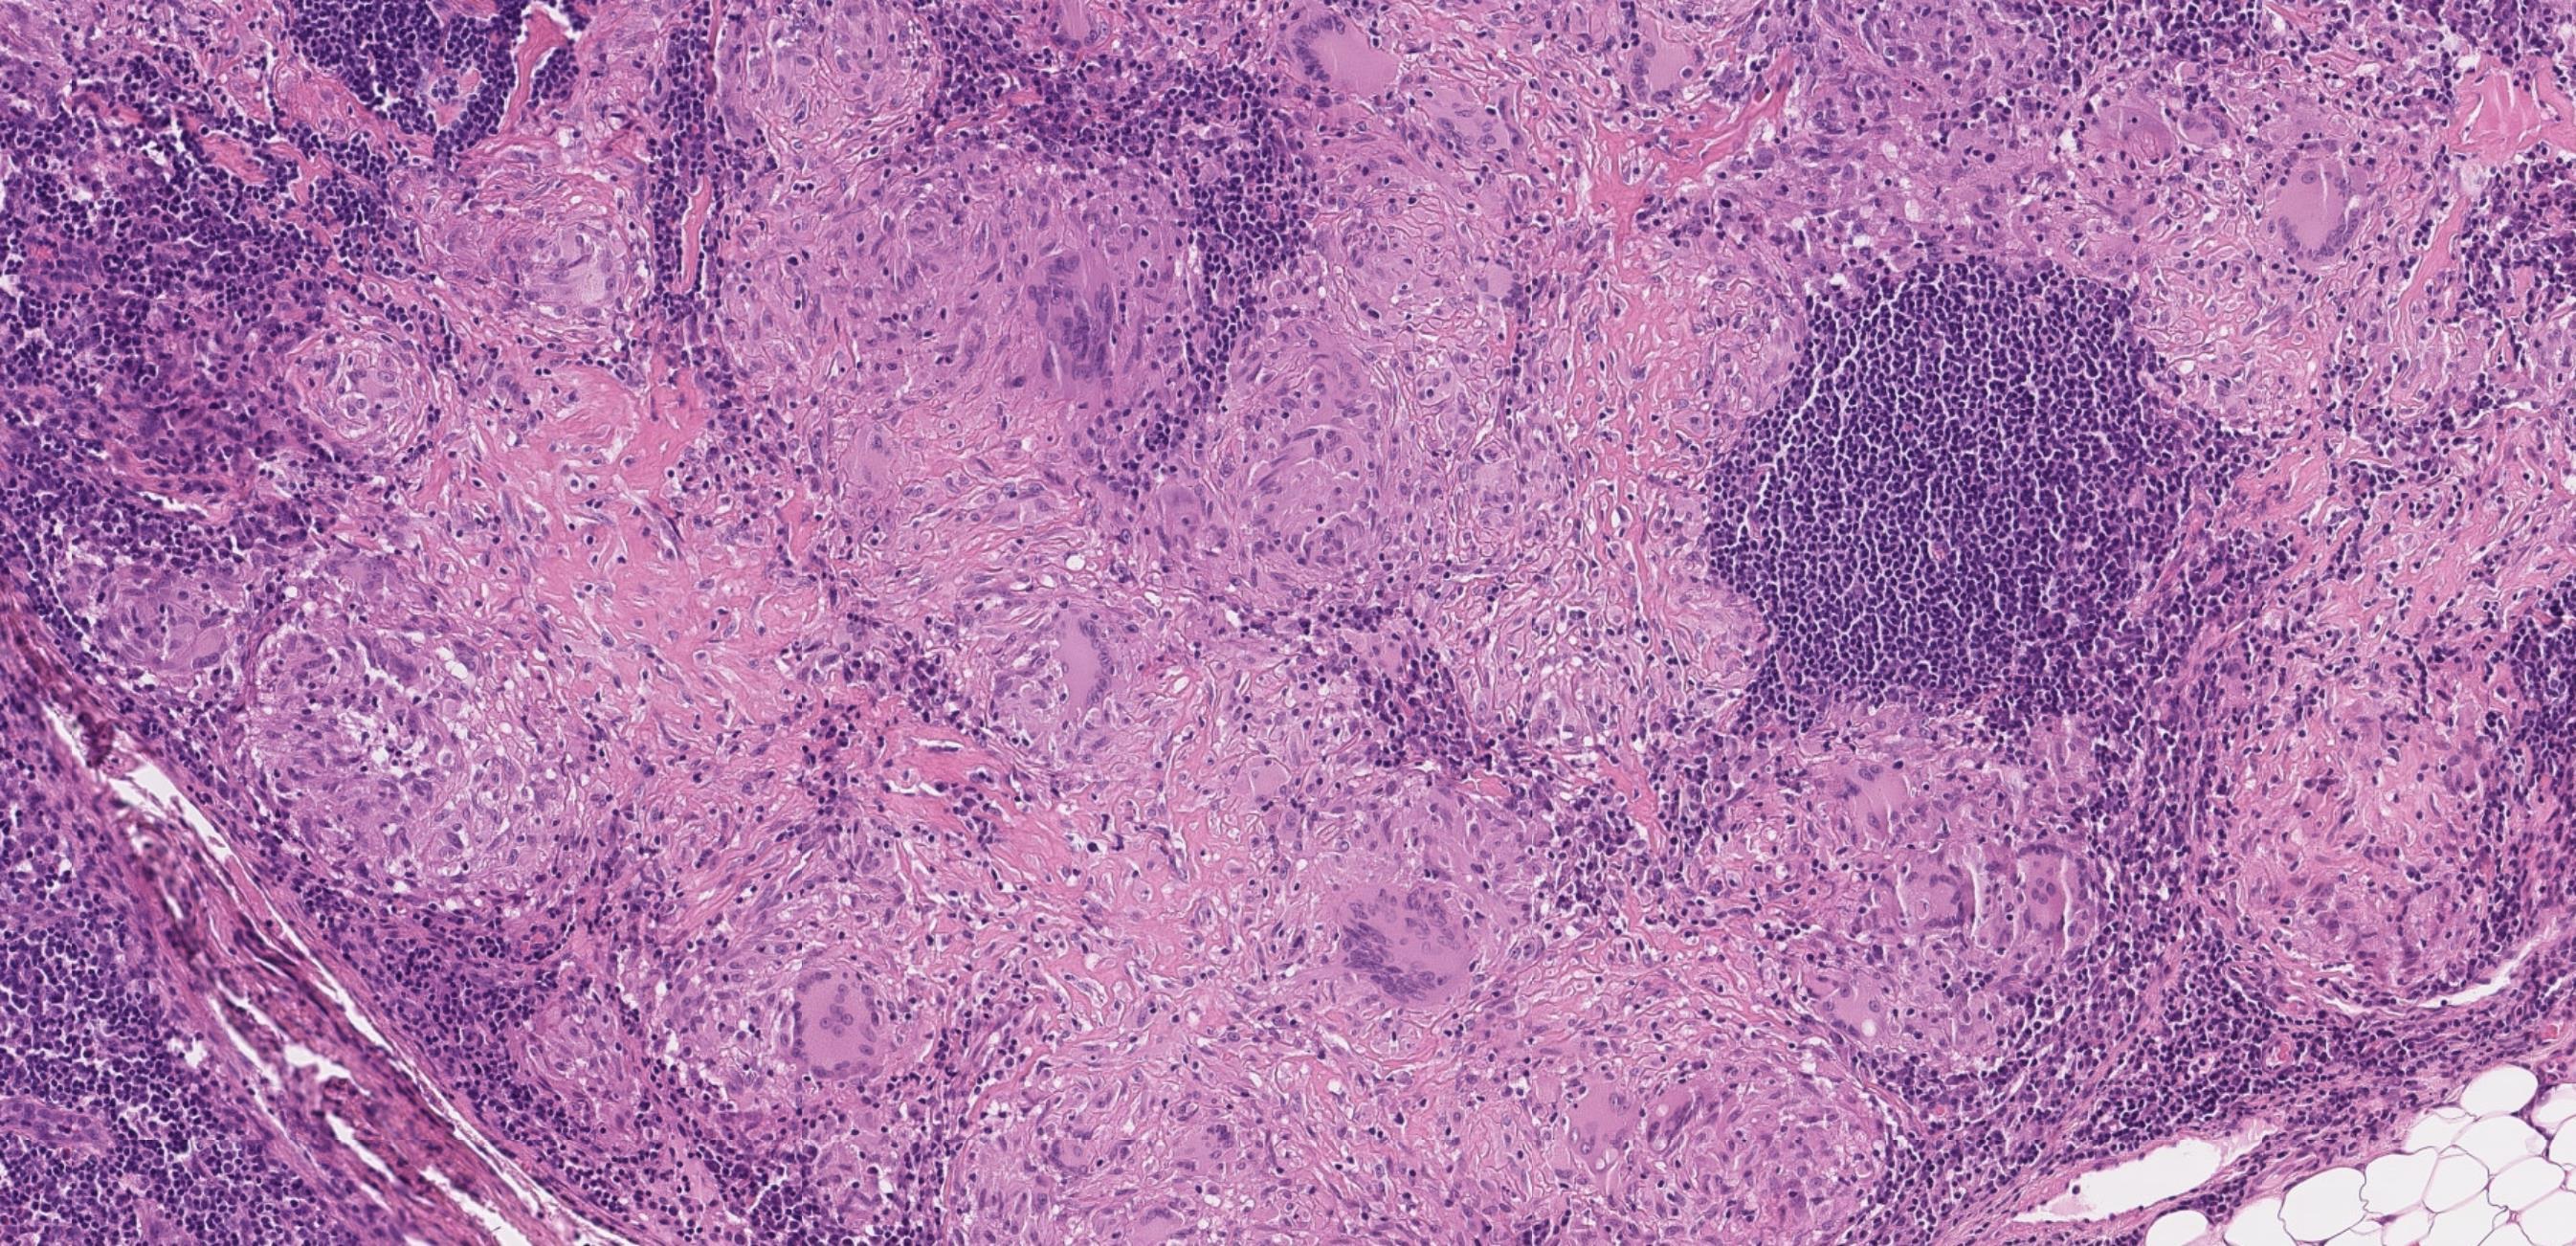

Case 9

Female, elderly. Thyroid, U3, THY3a.

Case 9 Diagnosis

Anaplastic thyroid carcinoma

Immunoprofile • ATC usually shows some cytokeratin expression (75% ) • A minor subset of cases focally express TTF1. • Thyroglobulin is almost always negative with very rare cases focally expressing in epithelioid cells • PAX8 is positive in half of ATCs • p53 is expressed in >50% cases • Ki-67 proliferative rate is usually high

Differential diagnoses

• Sarcoma (synovial sarcoma, malignant peripheral nerve sheath tumour, angiosarcoma, leiomyosarcoma and rhabdomyosarcoma) • melanoma; • medullary thyroid carcinoma; • mucoepidermoid carcinoma; sclerosing mucoepidermoid carcinoma with eosinophilia; • Riedel thyroiditis; • NUT carcinoma; • intrathyroid epithelial thymoma • spindle epithelial tumour with thymus-like differentiation.